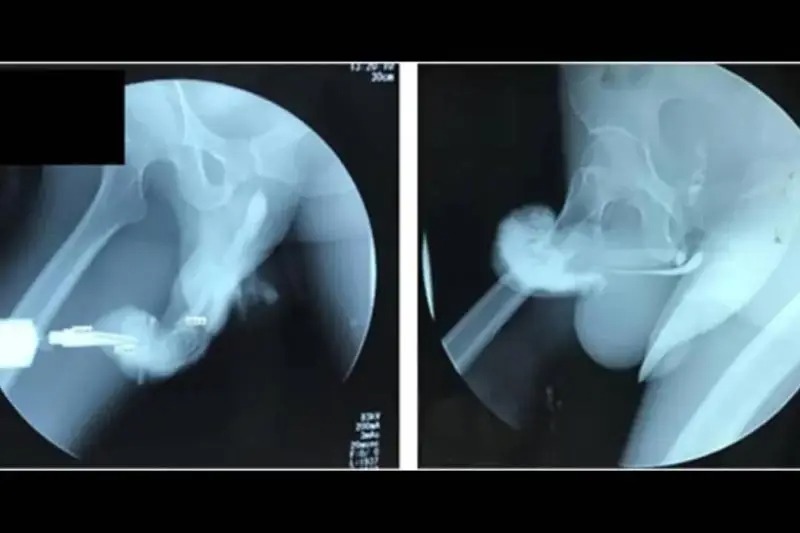

A los minutos del accidente el hombre sintió mareo y decidió buscar ayuda médica. Al llegar al hospital el cirujano le informó que tenía fractura en el pene por un error al sostener relaciones sexuales.

El hombre fue sometido a una cirugía en un hospital de Medellín, Colombia y ahora cuenta el incidente con humor.